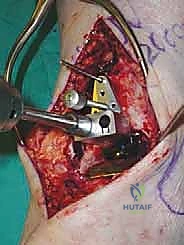

4. وضع أدلة القطع (Jig Placement and Alignment)

تعتمد دقة الجراحة على المحاذاة الصحيحة. يتم استخدام أجهزة توجيه متطورة (Jigs) تثبت على عظمة الساق باستخدام دبابيس معدنية. يتم التحقق من صحة الزوايا والمحاور باستخدام جهاز الأشعة السينية المباشر داخل غرفة العمليات (C-arm Fluoroscopy). يضمن الدكتور هطيف أن يكون القطع موازياً للأرض تماماً عند وقوف المريض.

5. القطع العظمي الظنبوبي (Tibial Bone Cut)

باستخدام منشار جراحي دقيق التذبذب، يتم إزالة شريحة رقيقة جداً (بضعة مليمترات) من السطح السفلي التالف لعظمة الظنبوب. يتم القطع بحذر شديد لتجنب إصابة الأوتار الخلفية أو الأوعية الدموية.